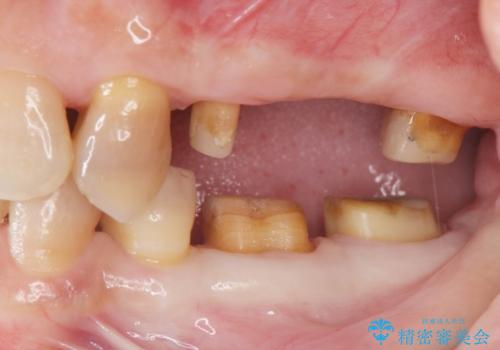

- ぐらぐらする歯や銀歯、なんとなくにおいのする奥歯の治療を求めて来院されました。

X線、歯周組織検査の結果、全体的に奥歯には重度〜中等度の歯周病の問題が見られました。

残すことのできない歯、予後の悪い歯を抜去し、ブリッジイ・ンプラントによる機能回復をおこなっていくと同時に、残すことのできる歯には歯周病治療をしっかりと行い、

将来に渡りしっかりと自分の歯で噛めるような口腔内環境を構築していきます。